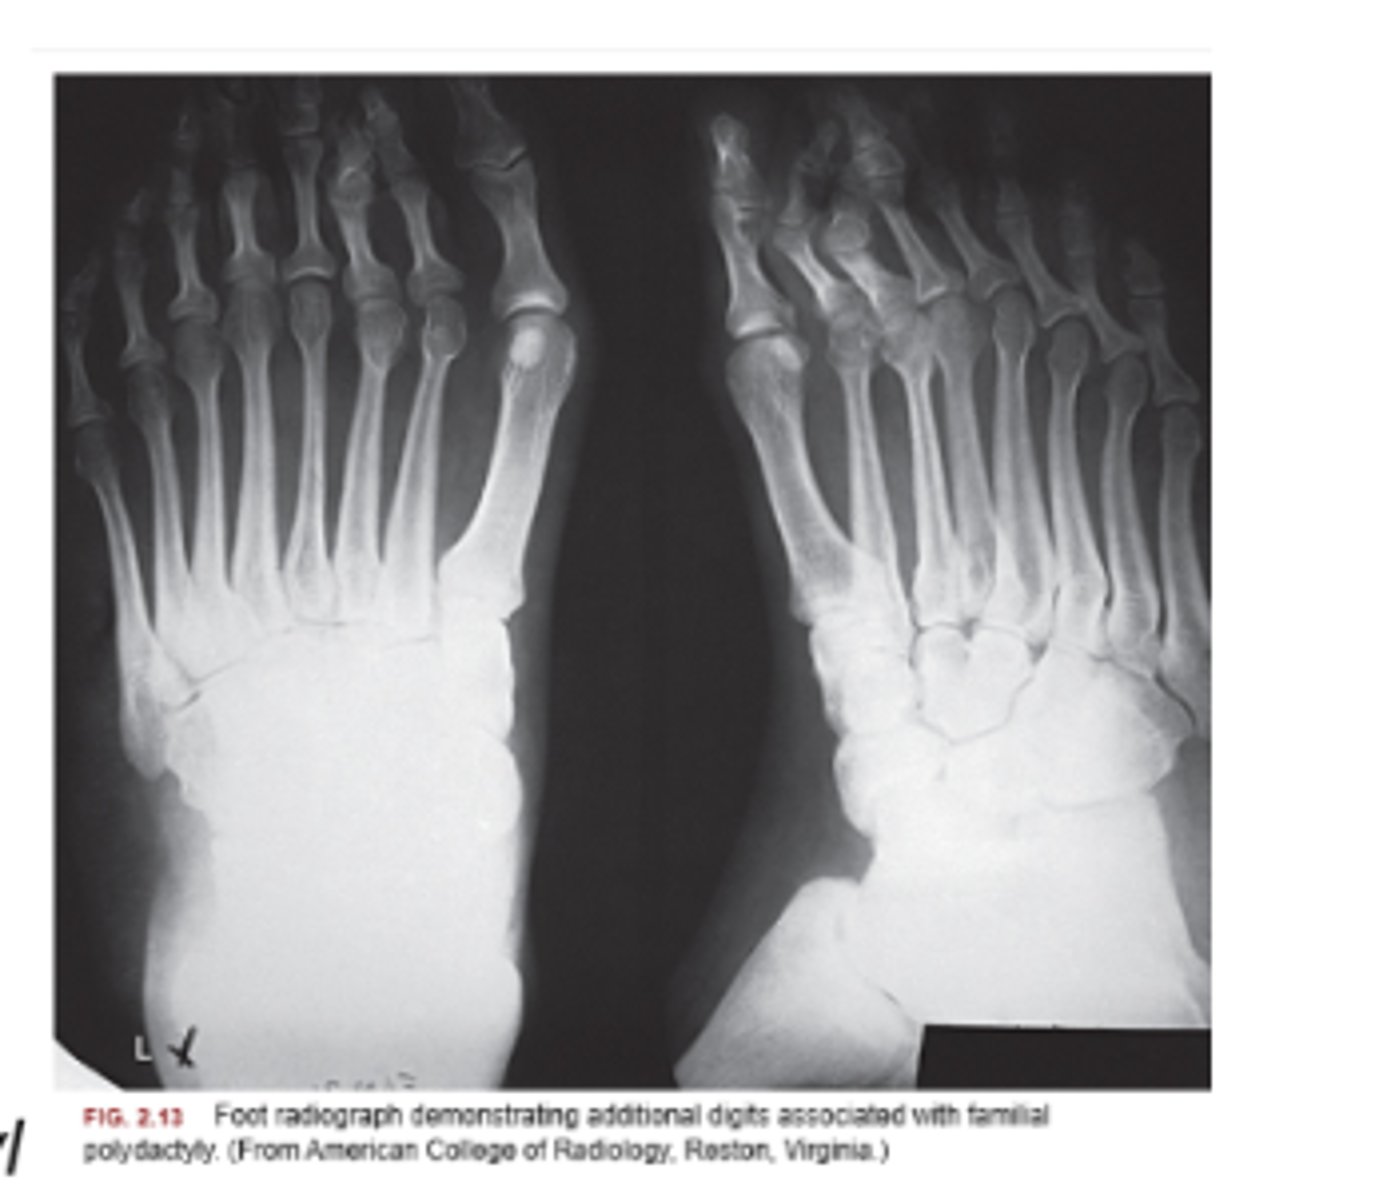

Polydactyly definition

presence of an extra digit or digits

polydactyly